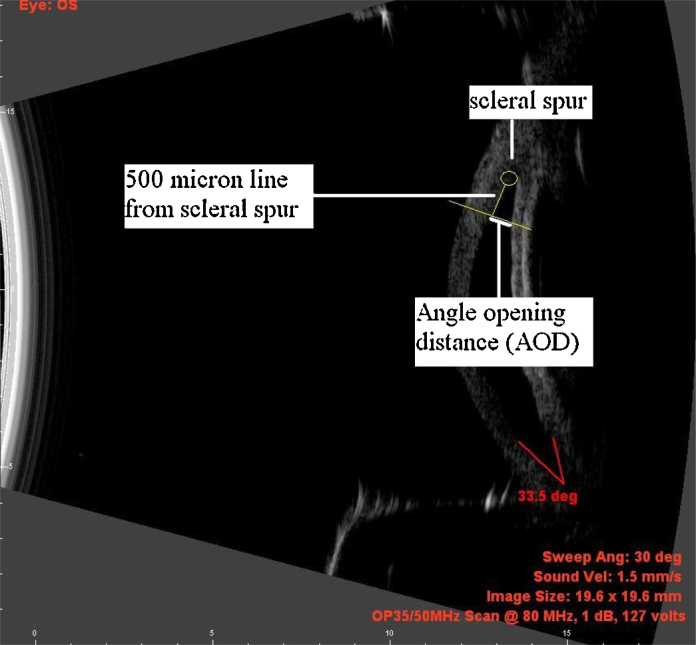

Angle opening distance (AOD): Measured by drawing a 500 μm line parallel to the endothelium starting at the scleral spur and extending toward the central cornea. At the 500 μm point, another line was drawn perpendicular to that point and the distance measured between the corneal endothelium and the point where the perpendicular crossed the peripheral iris (Fig. 2).

Fig. 2.

Measurement of Angle opening distance.